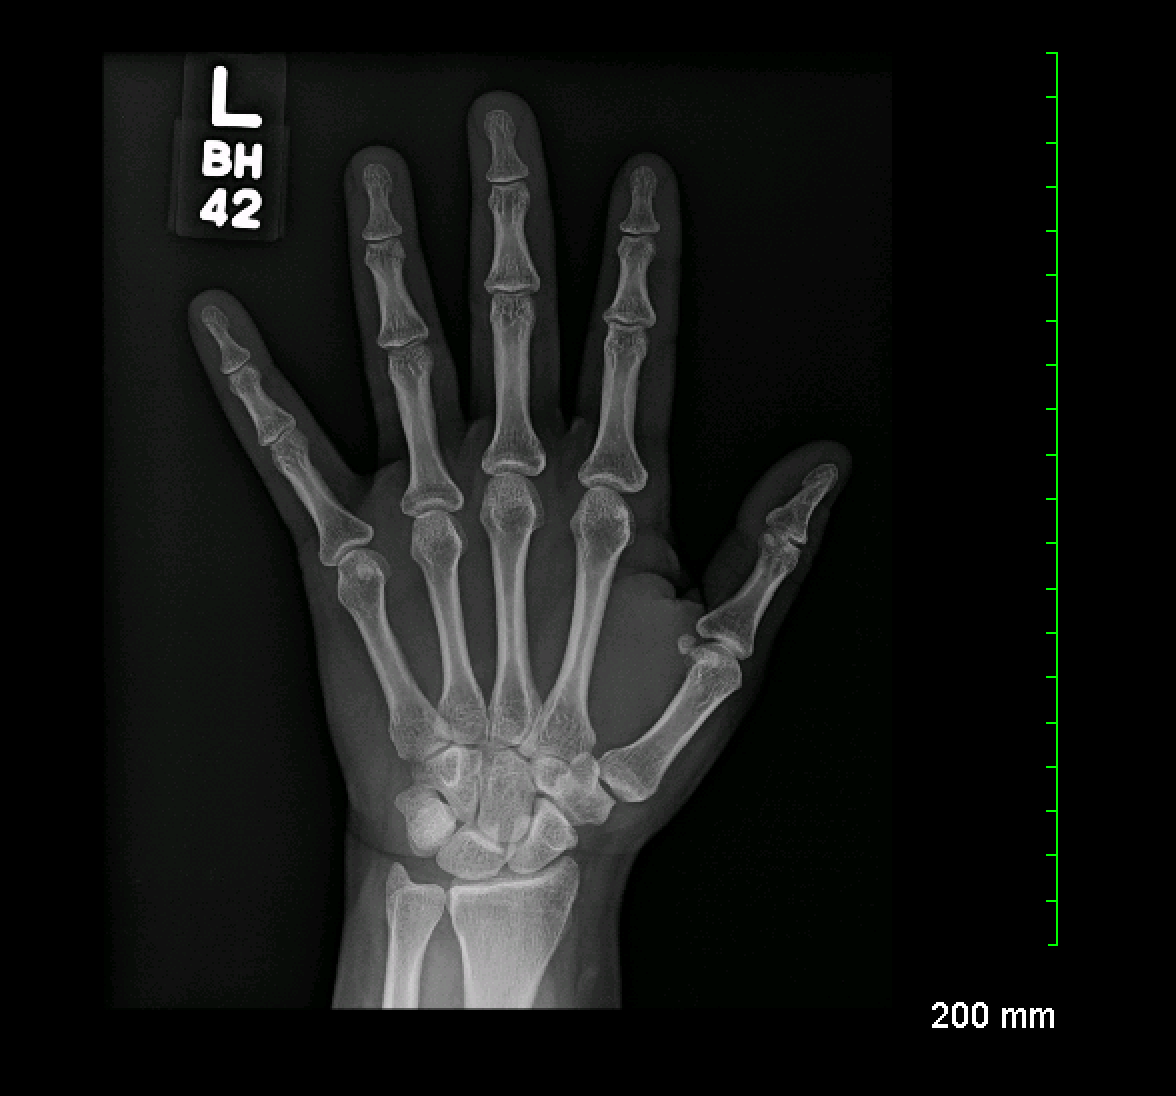

Left Hand X Ray Labeled . The hand comprises the metacarpal and phalangeal bones. Although additional radiographs can be taken for. Frontal radiograph of the hand with labels. Oblique radiograph of the hand with labels. The hand series consists of posteroanterior, oblique, and lateral projections. Head of the middle phalanx of index finger. There are 5 metacarpals in the hand.

Archive Of Unremarkable Radiological Studies Left Hand XRay Stepwards